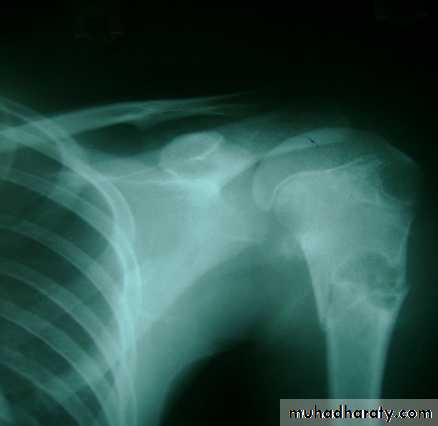

2. Fragility (low energy) fractures

Osteoporosis is a common disease in the elderly and is now recognised as the major factor to rising the number of so-called fragile fractures.The condition is characterized by loss of trabecular bone mass and connectivity as well as thinning of the cortical bone.

The commonest fragility fractures:

Colles fracture

Femoral neck fracture

Thoracic and lumbar vertebrae fractures